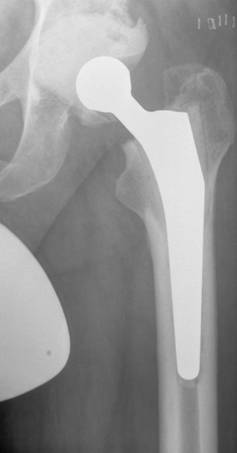

Some reports describe the stability of cementless fixation after septic revision surgery using mostly non-modular implants: Fehring et al. [38] achieved stable bone-ingrown fixation in 96% of their cases using non-modular and modular cementless prostheses with proximal fixation, while Nestor et al. [58] reported an implant stability of 79% using non-modular, proximal porous-coated stems. Wilson and Dorr [56] on the other hand, only achieved a 38% bone-ingrown fixation after 3 years in, admittedly, a small group of 13 patients using a cementless non-modular stem with proximal fixation. Moreover, the rate of early loosening of cementless revisions stems varies from 0% to 18% (Table 2). We found low rates of subsidence (6%) and loosening (0%) and a high rate of bone-ingrown fixation (94%) of a cementless modular revision stem system (Revitan curved, Zimmer GmbH, Winterthur, Switzerland), which we believe is due to the distal fixation procedures in viable bone on the one hand and to the modularity of the stems on the other hand [20] (Figure 2). Thus, as already described in an anatomic study, the in situ assembly of the components enabled the effective distal fixation of the distal prosthetic component in an adequate osseous bed before the proximal component is added and corrected for leg length and antetorsion [61].

Figure 2

Radiograph two years after re-implantation of a cementless modular revision stem and a press-fit-cup

We carry out two-stage revisions with cementless hip prostheses (Figures 1,2). Our technique differs from previously published techniques with cementless two-stage revision surgery in four ways (Table 2). Firstly, the antibiotic used in the antibiotic-loaded cement of the spacer and used for the systemic treatment is chosen on the basis of the sensitivity of the bacterium causing the infection. Since the use of several antibiotics seems to result in synergistic effects with regard to local release patterns, we always use at least two antibiotics in the cement and prefer COPAL® cement to Palacos® R-G cement (Heraeus Medical, Wehrheim, Germany) whenever possible because the former exhibits better release of gentamicin [27]. Secondly, we employ a short period of 2 weeks of intravenous antibiotic treatment. Thirdly, re-implantation is performed after a 6 week spacer interval and fourthly, we use modular revision stems with distal fixation in the femoral diaphysis. In a prospective study using this standardized protocol for two-stage cementless revision of periprosthetic infection of hip prostheses we were able to demonstrate 100 % eradication of infection [20]. We achieved implant stability with no early aseptic loosening, bone-ingrown fixation in 94% of the stems and absence of stem subsidence in 94%, as well as Harris hip scores of 90 points resulting in the conclusion that this concept is sufficient for treatment of periprosthetic late infections of hip prostheses [20].